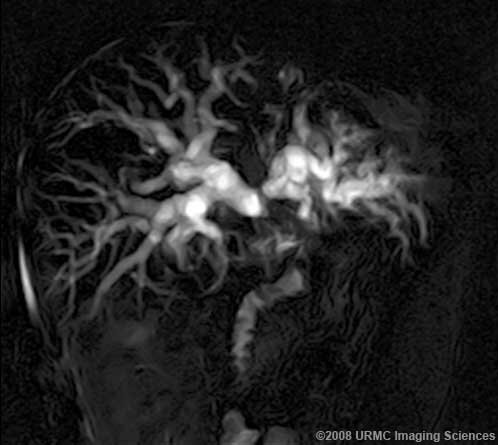

Результаты МРХПГ